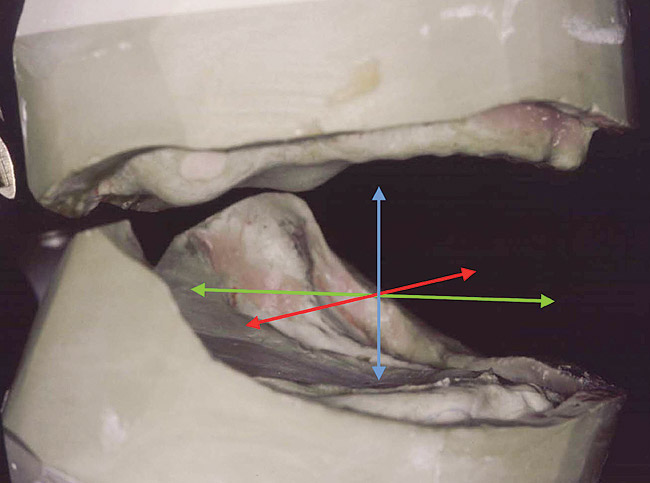

Vertical dimension of occlusion is a 3-dimensional (3D) space encompassing the infero-superior, medio-lateral, and antero-posterior functional vectors of mandibular positioning. This 3-dimensionality results from the functions of the many interlocking components of the craniofacial complex. This complex affects how we eat, breathe, speak, and, in large measure, how we look. It evolved from a simple receptacle for food absorption to a complex system of organs that is central to our well-being. Thorough knowledge of all the craniofacial complex’s individual components and functions is crucial to maintain or recreate an appropriately working 3D vertical dimension. The dentition is the foundation of the craniofacial complex.

Understanding the central role vertical dimension of occlusion (VDO) plays in oral health, including comfort, function, and esthetics, is a necessity when replacing or restoring the dentition. But what is vertical dimension? It is generally defined as the infero-superior position of the mandible to the maxilla when the teeth are in maximum contact. Maximum tooth contact (and the resulting relationship of the mandible to the maxilla) is not 1-dimensional, however. It is the 3-dimensional (3D) spatial positioning of the mandible-to-maxilla infero-superiorly, medio-laterally, and antero-posteriorly in response to muscle and tooth interaction (Figure 1).

Figure 1. Vertical dimension is 3-dimensional. The axes are cranio-caudal (blue), medio-lateral (red), and antero-posterior (green).